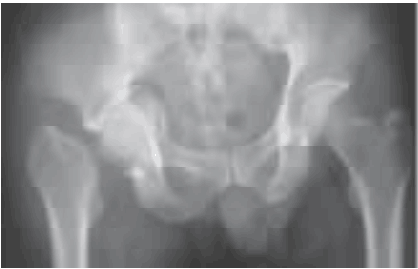

图1 术前正位X线片示右侧股骨颈、髋臼骨折,股骨头及髋臼内陷,股骨向上移位

查体:跛行步态,全身无皮疹,右下肢短缩外旋畸形,右髋部轻度肿胀,局部无瘢痕、窦道,右腹股沟中点、大转子轻度压痛,右侧髋关节被动活动范围基本正常,右下肢肌力Ⅳ级,深感觉减弱,右下肢生理反射减弱、病理反射未引出。骨盆正位X线片及髋关节CT示右侧髋臼、股骨颈骨折,股骨头及髋臼内陷,关节内可见游离骨块(见图1~2);髋关节MRI示右髋关节及相邻盆底软组织渗出肿胀(见图3);骨扫描未见异常;颈椎、胸腰椎核磁示轻度退行性变。